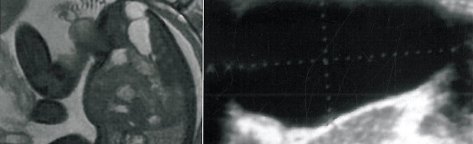

Il permet ainsi d'optimiser l'exploration de pathologies gynécologiques importantes, comme l'endométriose pelvienne ou la caractérisation des masses annexielles, qui restent la principale cause de chirurgie gynécologique (chapitres 4, 5, 6 et 7).

Si l'échographie endovaginale est l'examen de première intention dans ces pathologies ainsi que dans l'exploration des ménométrorragies (dont les pathologies endométriales et myométriales bénignes sont principalement responsables (chapitres 8 et 9),